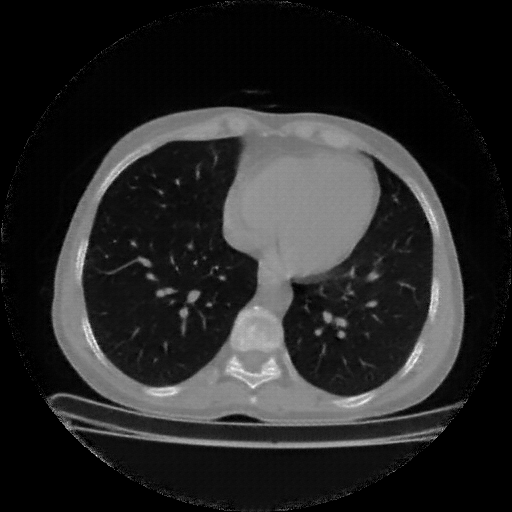

Reconstructed NATIVE CT scan (cycle consistency)

Full window (WL 1023.5, WW 4095 β†’ Low βˆ’1024, High +3071)

Actual HU range: [-1024.0, 1095.7]

Lung window (WL -600, WW 1500 β†’ Low βˆ’1350, High +150)

Actual HU range: [-1350.0, 150.0]

Mediastinum window (WL 40, WW 400 β†’ Low βˆ’160, High +240)

Actual HU range: [-160.0, 240.0]